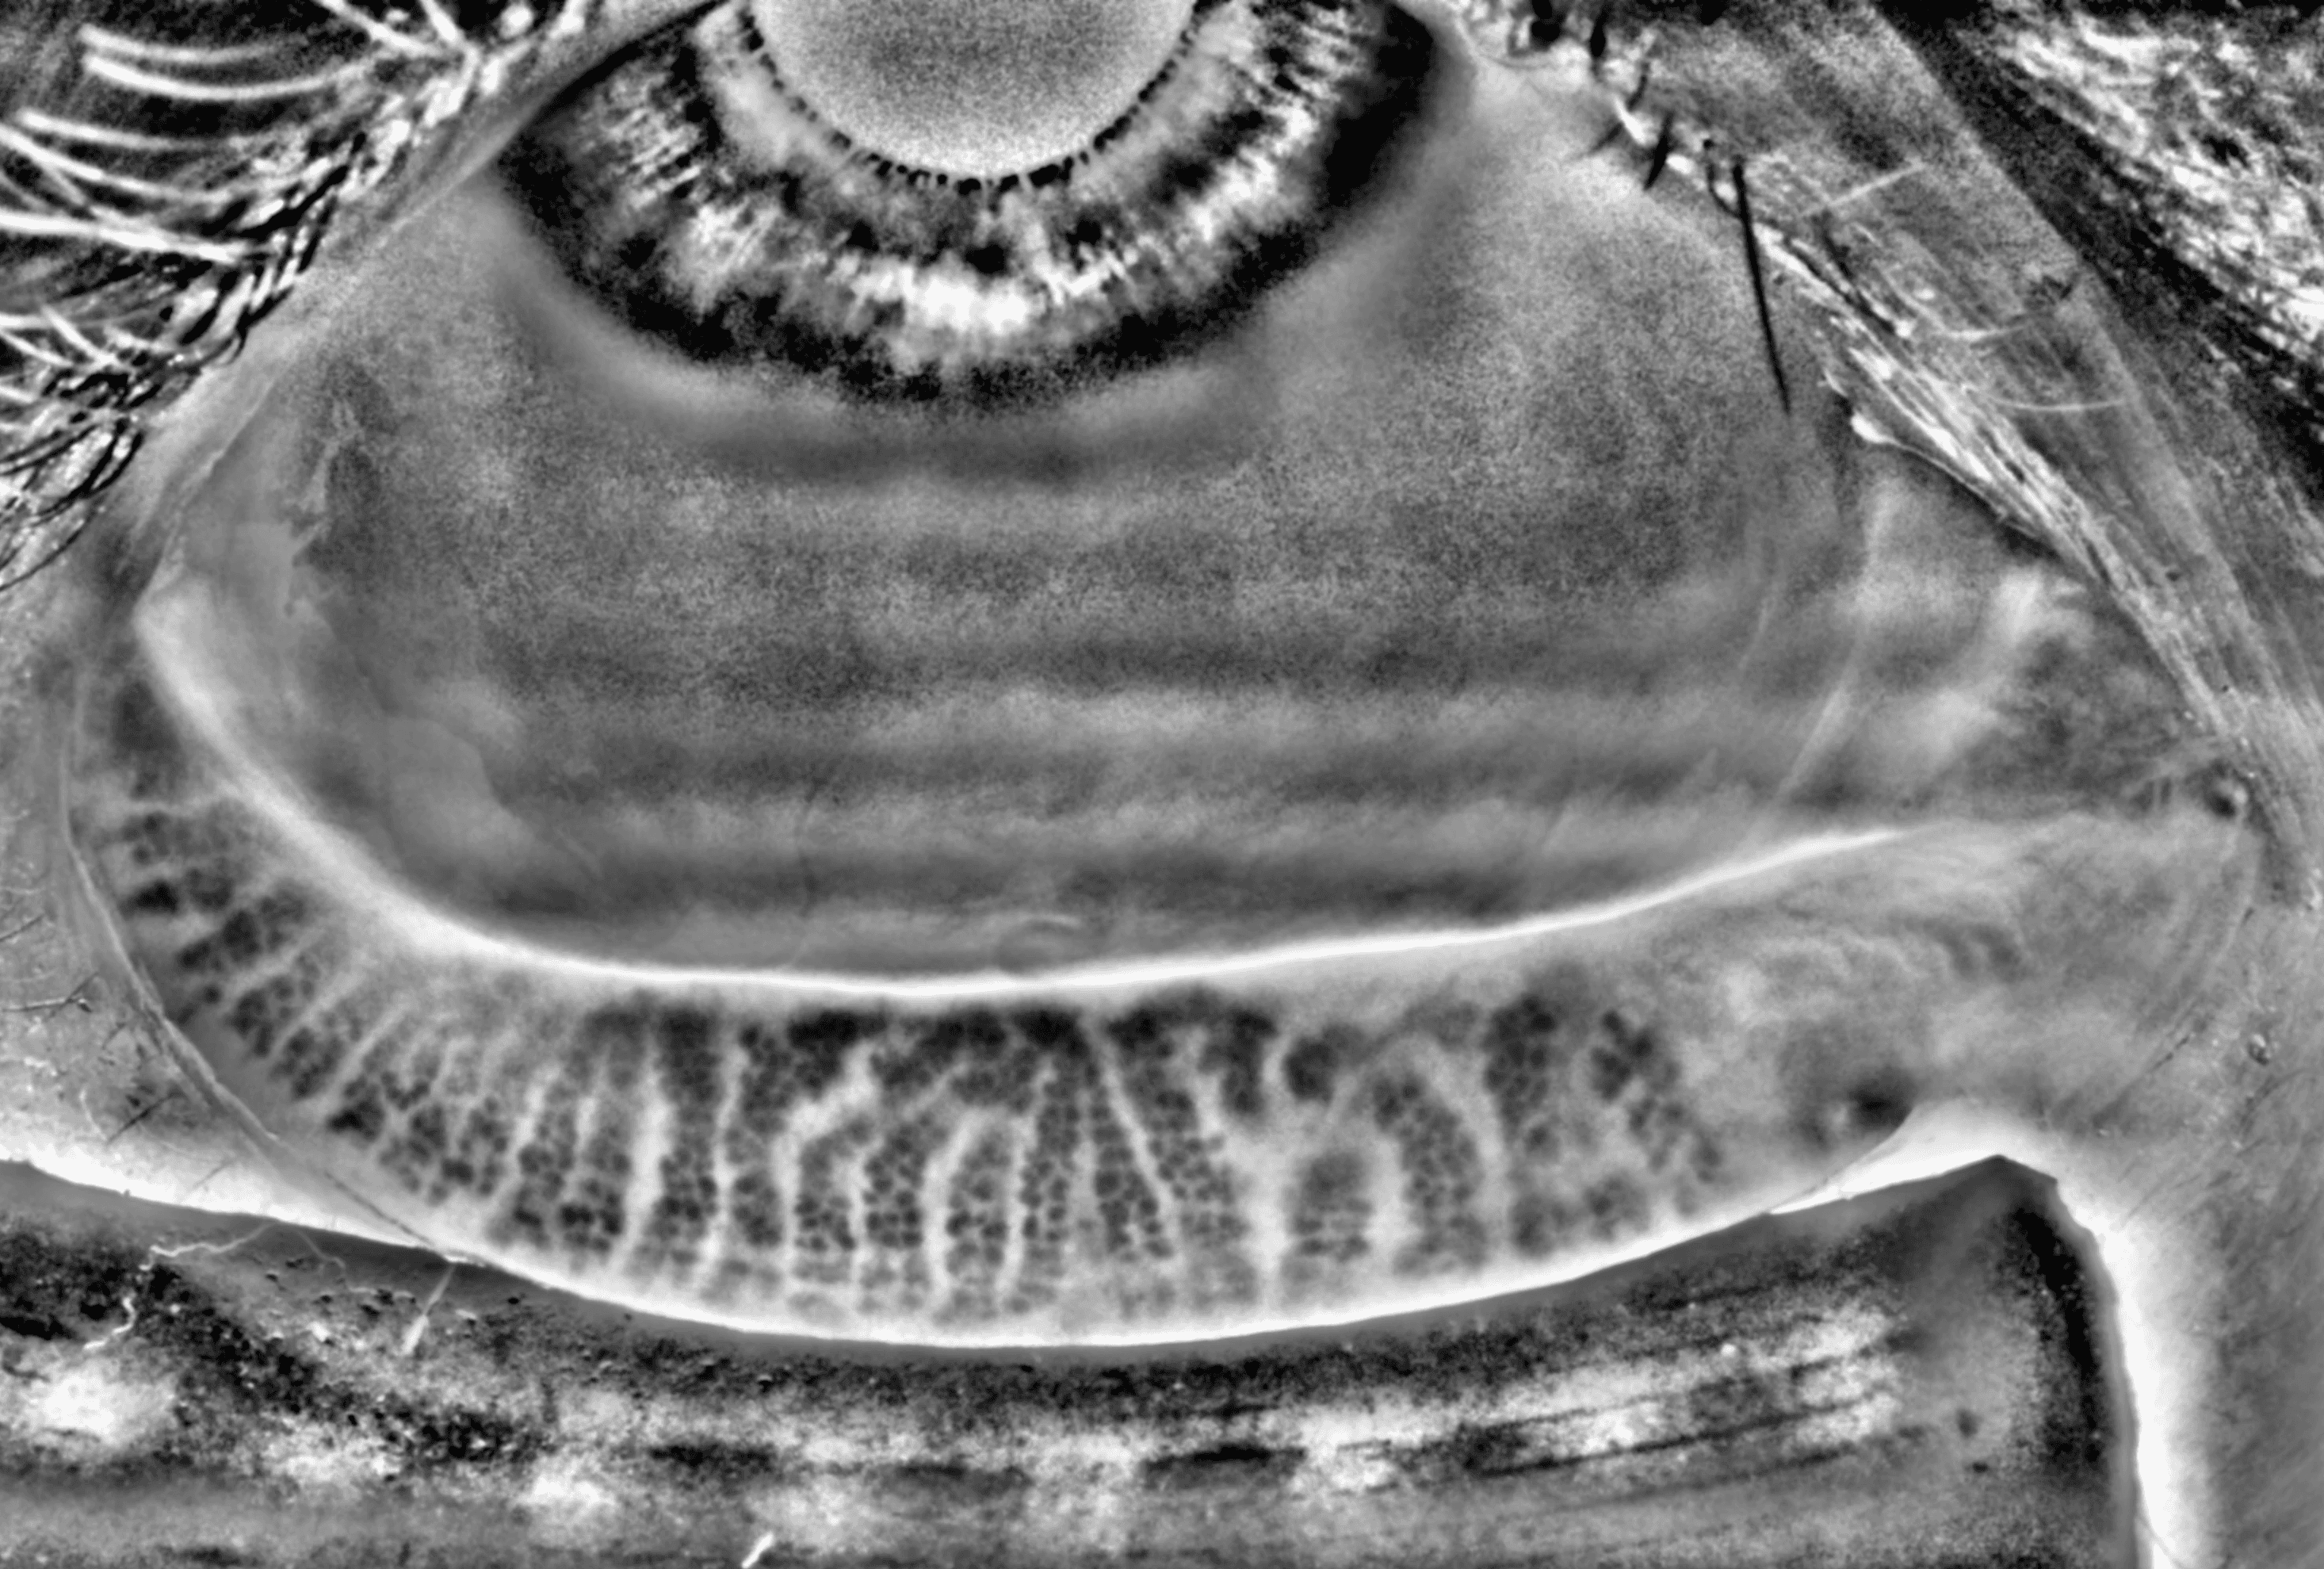

Capture and visualize meibomian gland structure, blink dynamics, tear film appearance, fluorescein imaging, and patient-reported symptoms using a single, compact device designed to integrate seamlessly into existing clinical setups.

See More with AI-Assisted

Real-Time Visualization

AI-assisted image processing enhances the visibility of ocular surface features, reducing time required manual image adjustments and allowing clinicians to focus on efficient clinical review. Operating directly on the live video stream, it provides immediate visual feedback that supports faster alignment, more confident image capture, and a smoother workflow.